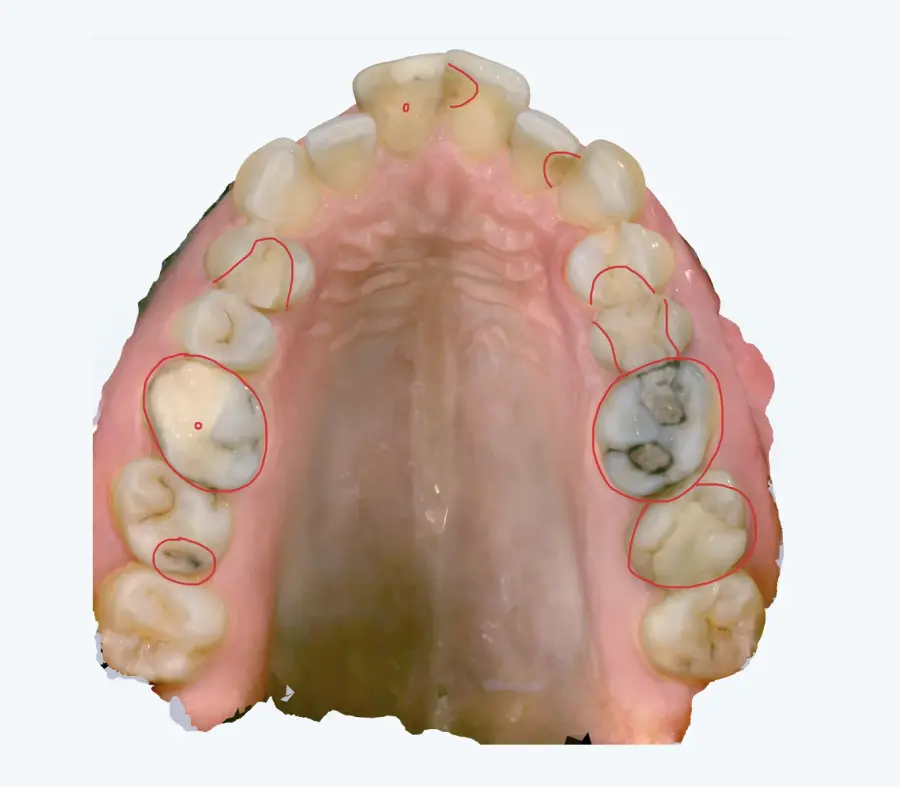

Papildus norādām, ka arī no intraorālās skenēšanas datiem (tostarp ekrānšāviņiem) ir identificējamas vairākas klīniski nozīmīgas problēmas, tai skaitā:

* aktīvi kariozi bojājumi,

* bojātas, lūzušas un plaisājušas plombes,

* vairāku zobu audu apjoma zudums,

* citas strukturālas izmaiņas, kas var ietekmēt turpmāko ortodontisko ārstēšanu.

Šie konstatējumi ir būtiski, jo pirms ortodontiskas ārstēšanas uzsākšanas ir nepieciešams nodrošināt mutes dobuma veselības stabilitāti, kas ir starptautiski pieņemta un medicīniski pamatota prakse.